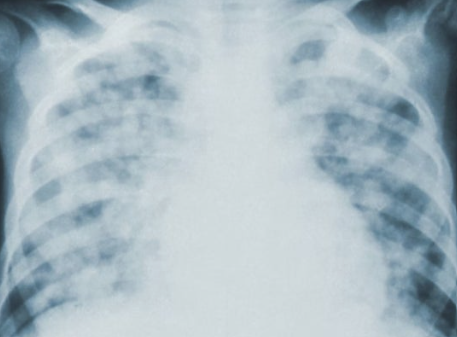

폐기흉의 증상은 갑작스럽게 나타나며 빠른 대처가 필요합니다. 대표적으로 갑작스러운 흉통과 호흡곤란이 있으며, 심할 경우 청색증, 호흡부전, 심장 기능 저하까지 이어질 수 있습니다. 폐기흉 환자의 약 절반은 재발할 수 있어, 초기 증상 발생 시 지체 없이 의료진의 진단을 받는 것이 중요합니다. 경미한 증상이라도 무시하지 않고 빠른 대응이 필요합니다.

폐기흉 치료는 상태에 따라 달라집니다. 가벼운 경우 산소 공급과 휴식으로 회복될 수 있으며, 심한 경우 흉부관 삽입이나 수술이 필요합니다. 또한, 재발 위험이 높아 예방적 수술을 고려하기도 합니다. 치료는 증상의 정도, 환자의 기저 질환 여부에 따라 맞춤형으로 진행됩니다. 적절한 치료를 통해 합병증을 최소화하고 안전한 회복을 도모할 수 있습니다.